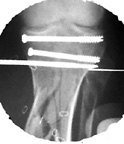

Tibia Fx ForumCase 1

I would appreciate treatment suggestions.My patient is a 30 year old with a very comminuted tibia fracture 6 weeks ago.It was grade 3B open. Initial treatment included irrigation, debridementClick images to enlarge.

and a hybrid external fixator including femur, tibia and foot. Screwswere placed in the plateau and plafond and a free flap plus STSG. Theskin is ok but atrophic. The femoral pins were removed and knee motionstarted at 6 weeks. There is no sign of callus. There is one pin inthe one large fragment of the diaphysis. All the pieces are lined upreasonably well. The XF pins are ok. Suggestions? Thank you.